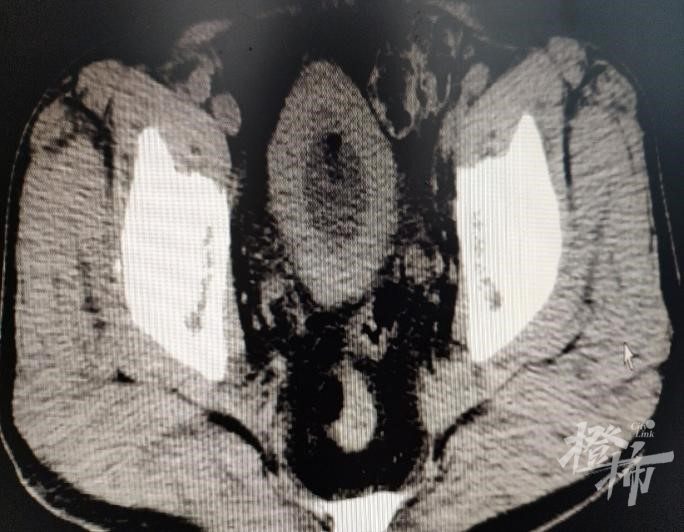

经过一系列专科检查,老马的疾病得到了确切的诊断:前列腺增生合并膀胱容量严重减小,膀胱内压力明显上升。这就需要在手术处理前列腺的同时扩大膀胱容量,降低膀胱内压力。只有一起解决了这三个问题才能彻底帮老马解决排尿和急迫性尿失禁的折磨。

针对这一特殊情况,段跃教授为老马制定了精确详细的手术方案,术中除了用1470纳米激光切除增生的前列腺组织外,还用激光切开膀胱肌小梁,以此来扩充膀胱容量和降低压力。手术很顺利,经过医护人员的精心照料,术后老马很快就康复出院了。